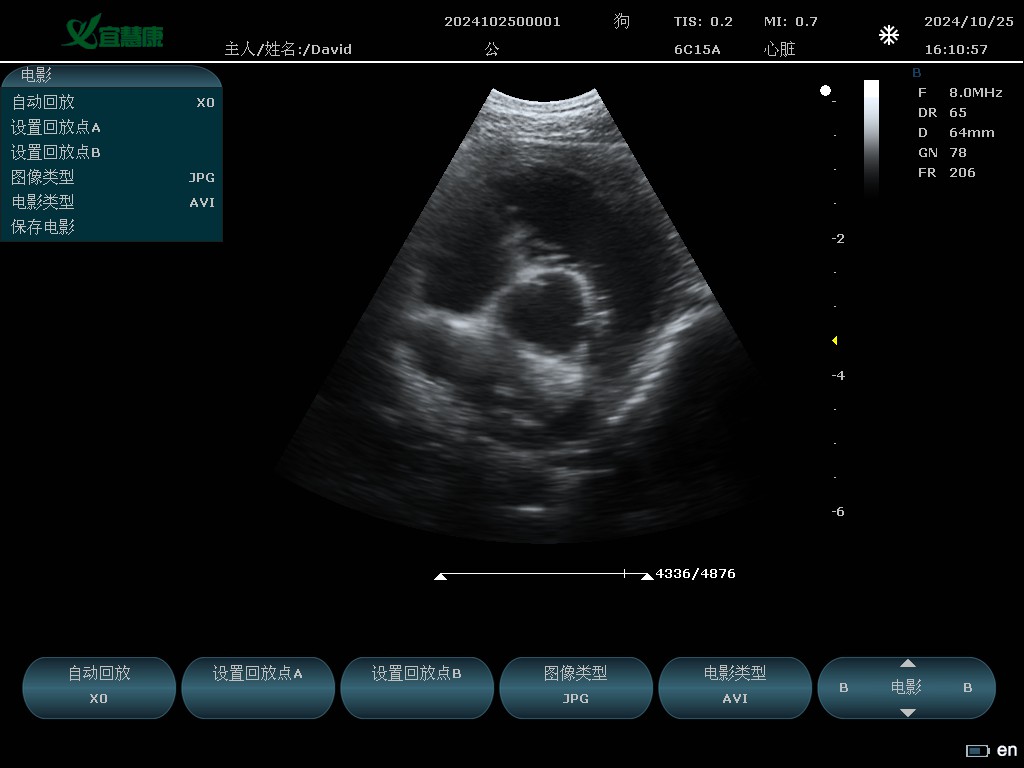

YHK-C90可以用于动物腹部、心脏、产科、小器官、血管、肌腱等方面的检查。支持的动物类型有猫、狗、牛、马、羊 其他。

6C15A: 6.5MHz/R15/80阵元微凸探头;

B模式

B、双幅、四幅、B+M、M、B+Color、B+PW、PW、B+Color+PW、★B/BC双实时

心脏B、M、PW模式应用测量